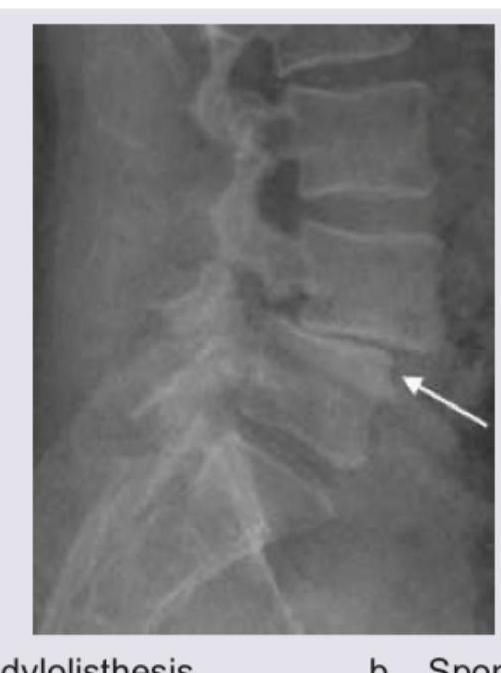

Which of the following spine deformities is seen in the image?

Explanation: ***Spondylolisthesis*** - The image shows a **forward slip** of one vertebral body over another, specifically at the L5-S1 level, which is the hallmark of spondylolisthesis. - The white arrow points to the area where the superior vertebra has translated anteriorly on the inferior one, indicative of this condition. *Spondylosis* - Spondylosis refers to **degenerative changes** in the spinal column, such as **osteophytes** (bone spurs) and **disc space narrowing**. - While some degenerative changes might be present, the primary and most striking finding visible is the displacement of the vertebral body, not just degenerative changes. *Compression fracture* - A compression fracture would typically present as a **wedging deformity** or a significant **reduction in the height** of the vertebral body. - The image does not show a loss of vertebral height or a clear fracture line within the vertebral body itself, but rather a displacement. *Osteoporosis* - Osteoporosis is a systemic condition characterized by **reduced bone density**, making bones fragile and prone to fractures. - While it can predispose to compression fractures, the radiographic finding in the image is not primarily about bone density or a typical osteoporotic fracture, but rather a **vertebral slip**.

Explanation: ***Spondylolysis*** * The image shows a **break in the pars interarticularis** of a vertebra, indicated by the arrow, which is characteristic of spondylolysis. * This condition is a **stress fracture** or defect in the pars interarticularis, a bony segment connecting the superior and inferior articular facets. *Renal osteodystrophy* * Renal osteodystrophy refers to a spectrum of **bone abnormalities** that occur in chronic kidney disease, not a specific vertebral fracture pattern. * It typically involves features such as **osteomalacia**, **osteitis fibrosa cystica**, or **osteoporosis**, which are not directly depicted as a fracture in this image. *Spondylolisthesis* * Spondylolisthesis is the **anterior slippage** of one vertebral body over another, which can be caused by bilateral spondylolysis but is not directly shown as a slip in this specific image. * The image distinctly highlights the **fracture line** itself, rather than the displacement of the vertebral body. *Tuberculosis (TB)* * Spinal tuberculosis (Pott's disease) typically presents with **destruction of vertebral bodies**, disc space narrowing, and often a **paravertebral abscess**. * The image does not show these features; instead, it demonstrates a clear **bony defect** in the pars interarticularis.